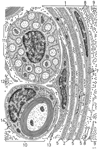

神経上膜;神経外膜【しんけいじょうまく;しんけいがいまく】 Outer connective-tissue sheath surrounding a nerve.(末梢神経束の最外側を包む膜で細網線維の凝縮によってつくれれているきわめて厚い結合組織である。神経束全体を包む束上膜と束内を細分する束間膜とに区別される。神経内膜・神経周膜とともに末梢神経を包む間質として働いている)